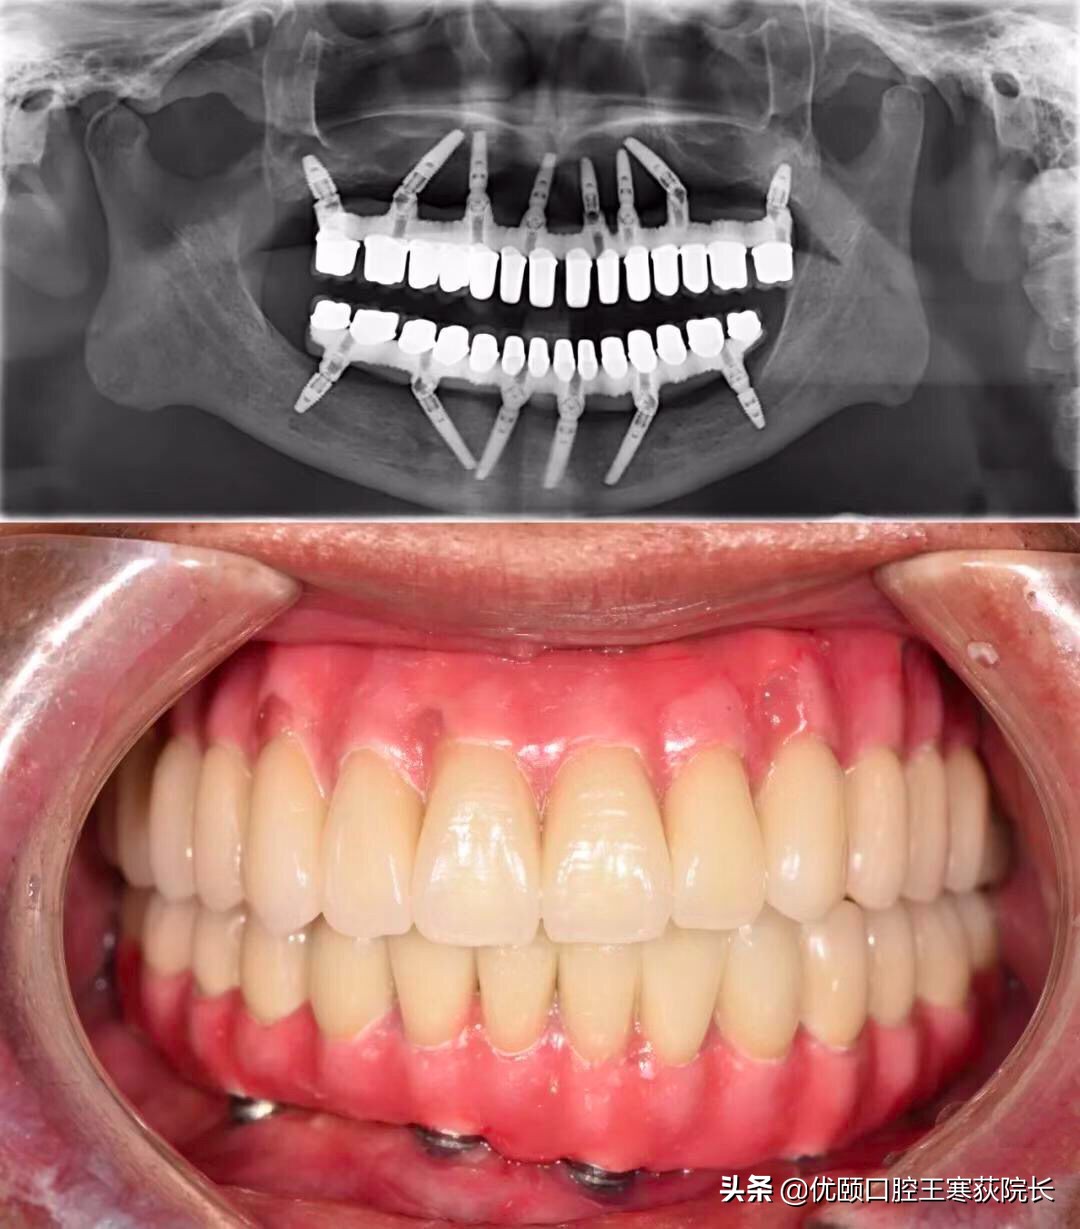

殊不知全*活口**动义齿,不仅功能比天然牙齿相差一大截,咀嚼效力不高,使用也不方便。全口种植义齿也是一种选择,可以较好地恢复咀嚼功能。

但现实是,并不是每个无牙患者,都拥有「口腔里开一辆奔驰」的财力。

全口种植义齿的花费,相当于「口腔里开一台奔驰」(@种牙匠黄建生 供图)